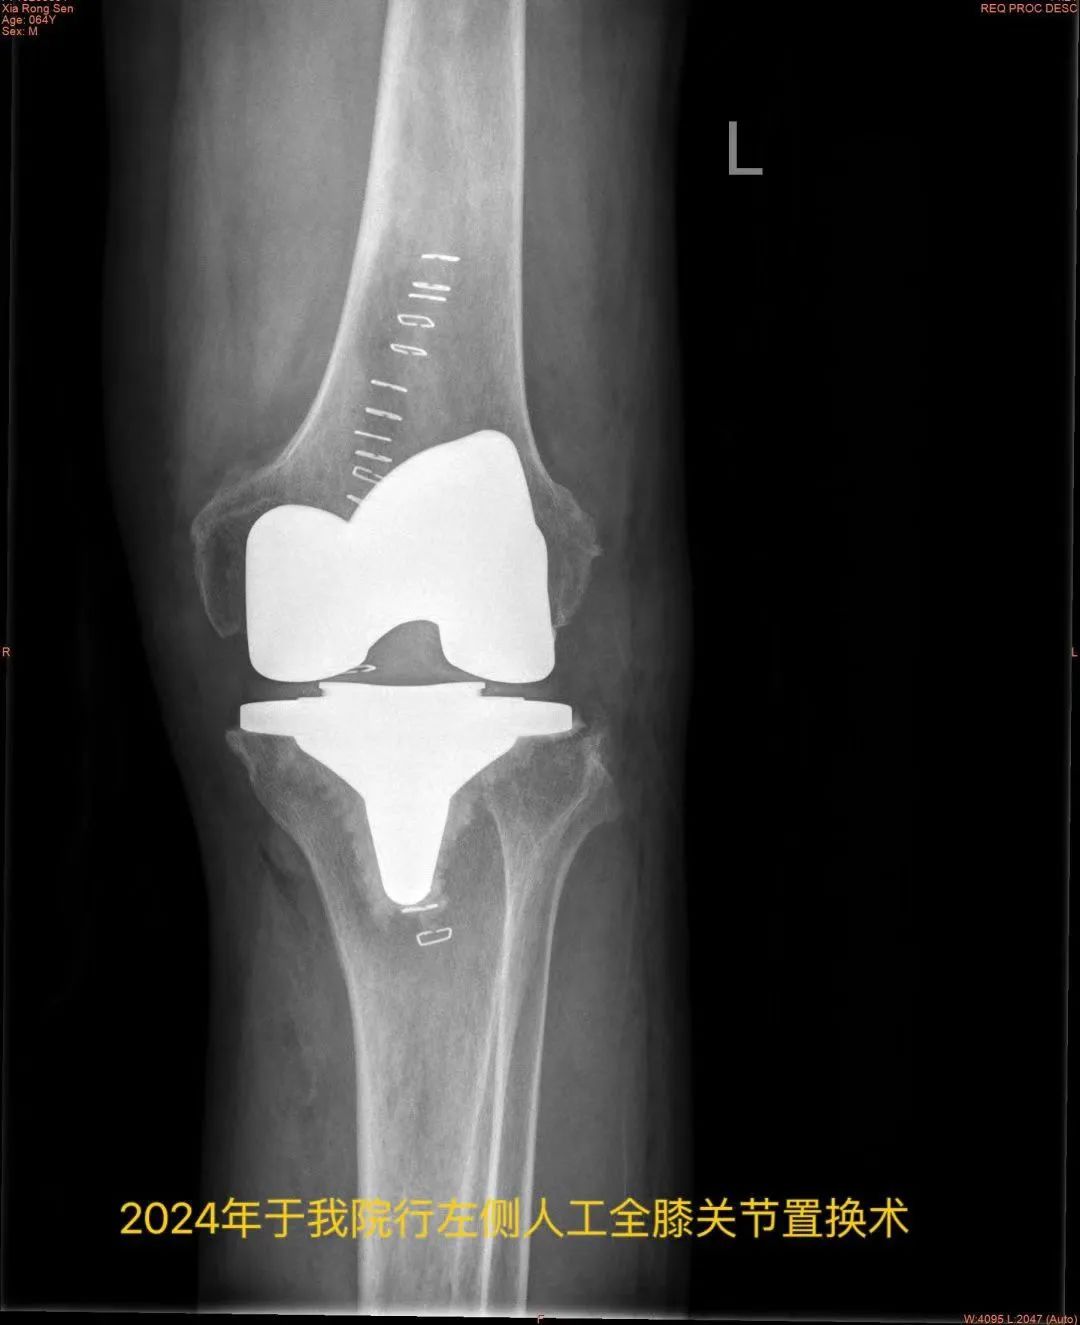

近日,王大爷因“左膝关节步行活动后疼痛加剧”门诊拟“黑尿病性膝关节炎”再次入住我院骨科,入院后查体:全身皮肤出现黑色素沉着,以面部及耳廓皮肤黑色斑块沉着明显,左膝关节周围肿胀,有压痛,左膝关节屈曲100°,伸直约10°(正常膝关节活动度为屈曲135°,伸直0°)。

与患者及家属充分沟通后

骨科副主任医师陆文青为

患者进行了周密的术前准备

并制定完善的手术预案

历经1.5小时

骨科团队成功为

王大爷实施了左侧人工全膝关节置换术

现患者术后第三天

可下地行走进行康复训练

复查示左膝关节假体位置良好